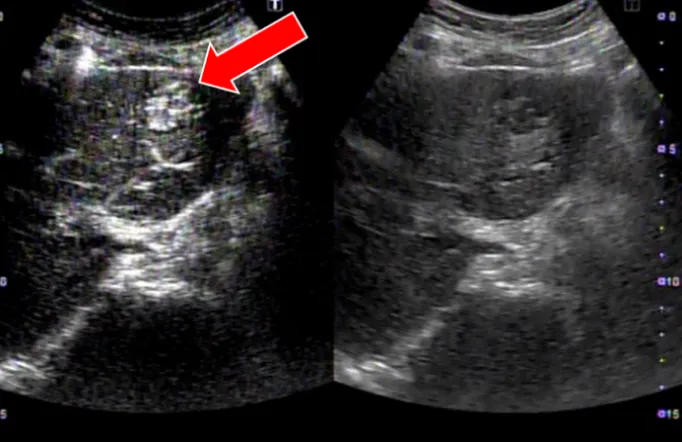

肝がんの検査には、血液検査と超音波(エコー)検査(写真2)、CT検査(写真3)、MRI検査といった画像検査を組み合わせて行います。CT検査やMRI検査では造影剤を使用して詳細な検査を行いますが、腎機能低下や透析症例でも安全に使用できる「造影剤」を用いて行う造影エコー検査(写真4)も週1回外来で行っています。

• (写真2)肝がんのエコー写真

• (写真4)肝がんの造影エコー写真